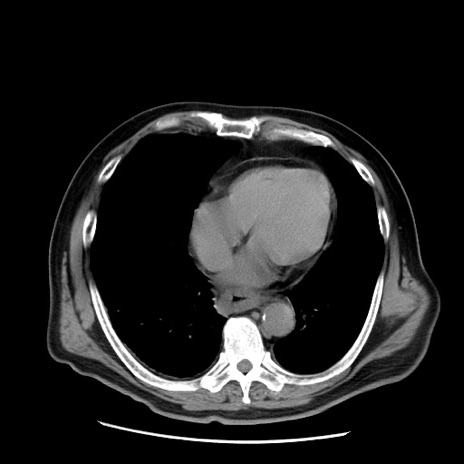

症例20(横断像)

【症例】 60歳代男性

【主訴】 腹部膨満、嘔吐

【現病歴】5日前頃より倦怠感を認め食事量減少し4日前の朝嘔吐、食事摂取困難となった。 3日前近医受診し点滴施行され整腸剤などを処方された。 当日他院を受診し、腹部膨満著明、炎症反応の上昇(CRP10.8、WBC11200)あり、紹介受診となる。

【身体所見】 意識JCS1 受け答えがはっきりしないBP 111/57mHg、 P 67bpm、、BT35.2°C、SpO2 97%(RA)、 腹部:膨隆、打診で鼓音あり、全体的に圧痛有り、腸蠕動音(-)、反跳痛ははっきりせず。

【データ】WBC 11400、CRP 14.20